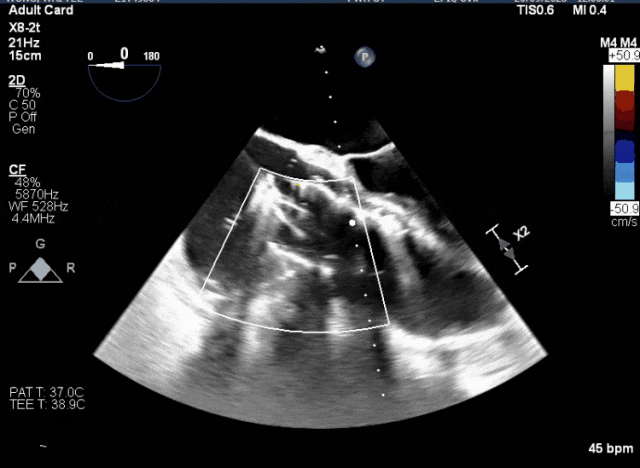

術(shù)中TEE觀(guān)察夾持件的位置

術(shù)后超聲評(píng)估瓣膜穩(wěn)定性良好,無(wú)瓣周漏